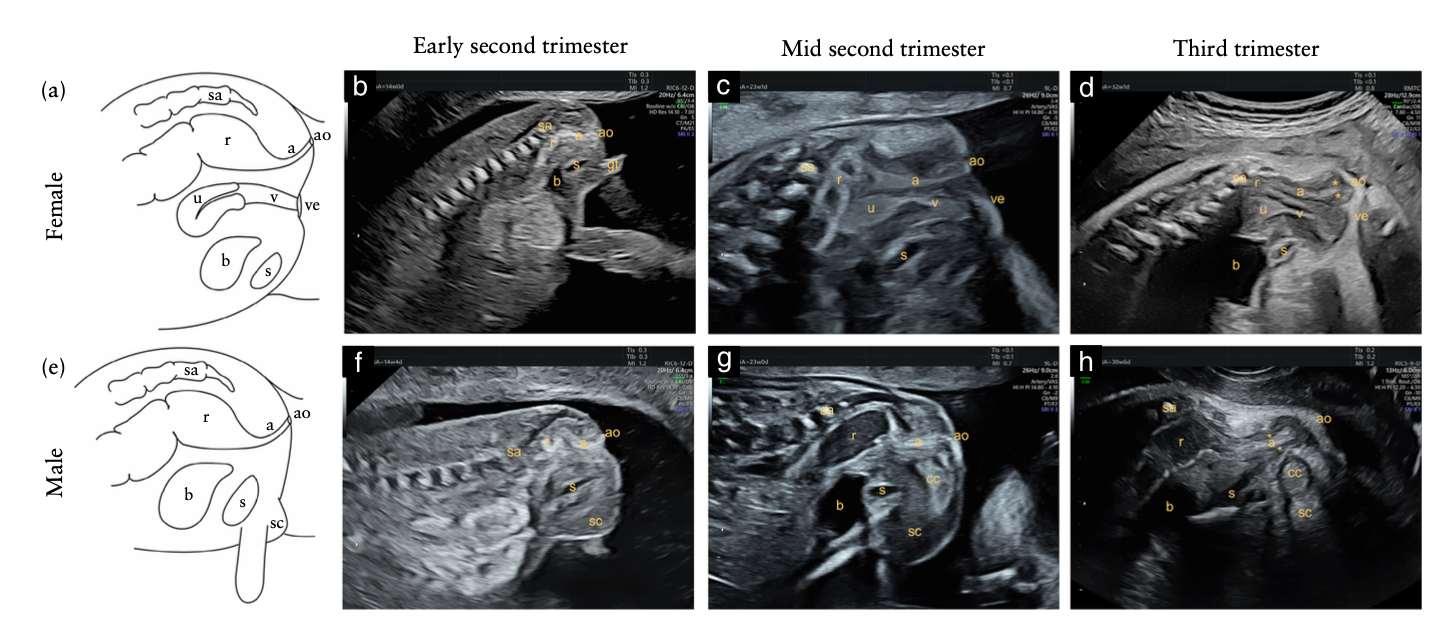

•  Mặt cắt dọc qua của sổ tầng sinh môn hoặc dưới xương cùng(infracoccygeal / transperineal) (3)

• Ưu điểm:

• Thấy toàn bộ ống hậu môn – trực tràng

• Phát hiện sớm (từ ~14 tuần)

• phân biệt:ARM cao (ARM thấp #65% và ARM cao-trung gian# 35%)

• Nhược điểm:

• Mới, chưa phổ biến

• Chỉ được chứng minh trong nhóm nguy cơ cao

• Có thể hạn chế ở thai lớn do lúc này xương cùng bị vôi hoá

Hình 6: khảo sát hâu môn trực tràng bằng phương pháp cắt dọc. Nguồn: Elkan Miller (2024)